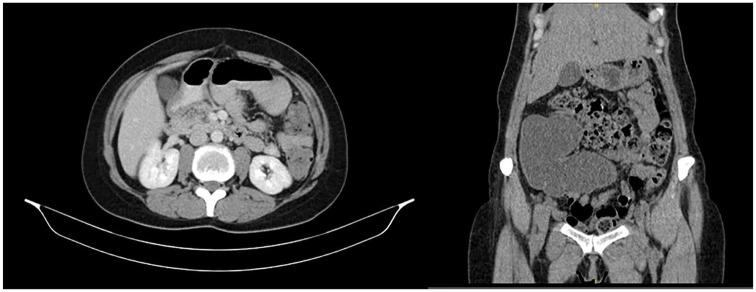

大陆尿转移是膀胱替代的首选方法,许多患者接受膀胱切除术良性条件。在大陆转移后,通常需要额外的干预措施以达到控制。其中一种手术是向新膀胱注射肉毒杆菌毒素。以前的囊膀胱注射都是经皮进行的。在这里,我们提出了一种微创内窥镜注射技术,在这种技术中,柔性设备已经成功地将肉毒杆菌毒素注射到囊袋膀胱中,通过囊袋口。我们证明了注射的可行性及其在减少眼袋收缩和患者症状方面的疗效。一位36岁女性在印第安纳州膀胱转移后1年出现持续性尿失禁症状。尽管先前的保守措施和回盲瓣强化手术,尿失禁仍然存在。内镜下注射,方便通过袋口,证明有效减少肌肉收缩和缓解痉挛样感觉,没有观察到的副作用。本病例证明了在内镜下印第安纳袋内注射肉毒毒素的可行性、安全性和有效性。

Continent urinary diversion is the preferred method of bladder substitution for many patients who undergo cystectomy for benign conditions. Additional interventions are often necessitated after a continent diversion to achieve continence. One such procedure is the injection of botulinum toxin into the neobladder. Previous injections into the pouch bladder have been performed percutaneously. Here we present a less invasive endoscopic injection technique where flexible equipment has been used successfully to inject botulinum toxin into the pouch bladder via the pouch stoma. We demonstrate the feasibility of the injection and its efficacy in reducing pouch contractions and the patient's symptoms. A 36-year-old female presented with persistent urinary incontinence symptoms 1 year after Indiana pouch diversion. Despite previous conservative measures and ileocecal valve reinforcement surgery, incontinence persisted. The endoscopic injection, facilitated through the pouch stoma, proved effective in decreasing muscle contractions and alleviating spasm-like sensations without observed side effects. This case shows the feasibility, safety and efficacy of botulinum toxin injection into Indiana pouch endoscopically.